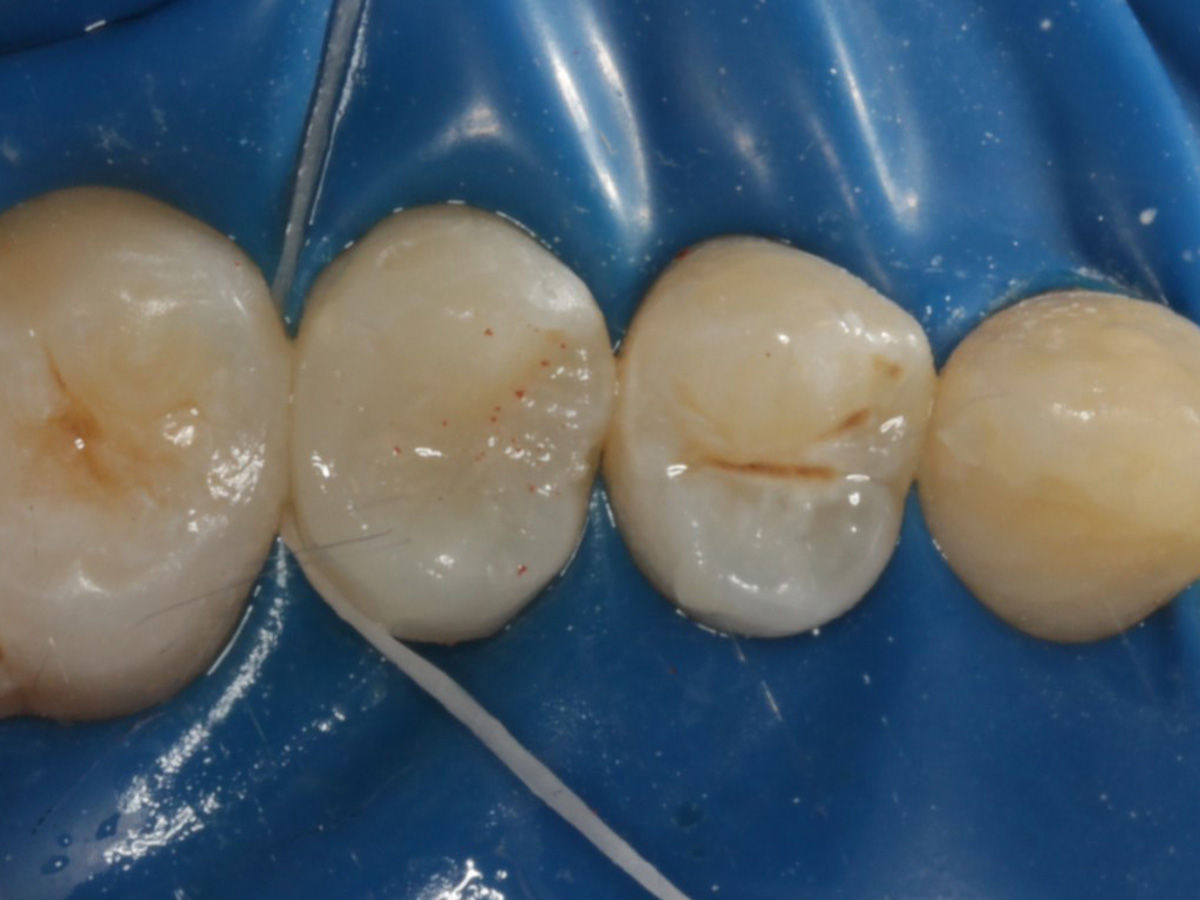

Abbildung 5

Defektdarstellung

Abbildung 6

Kariesexcavation pulpennah mit Kunststoffrosenbohrer